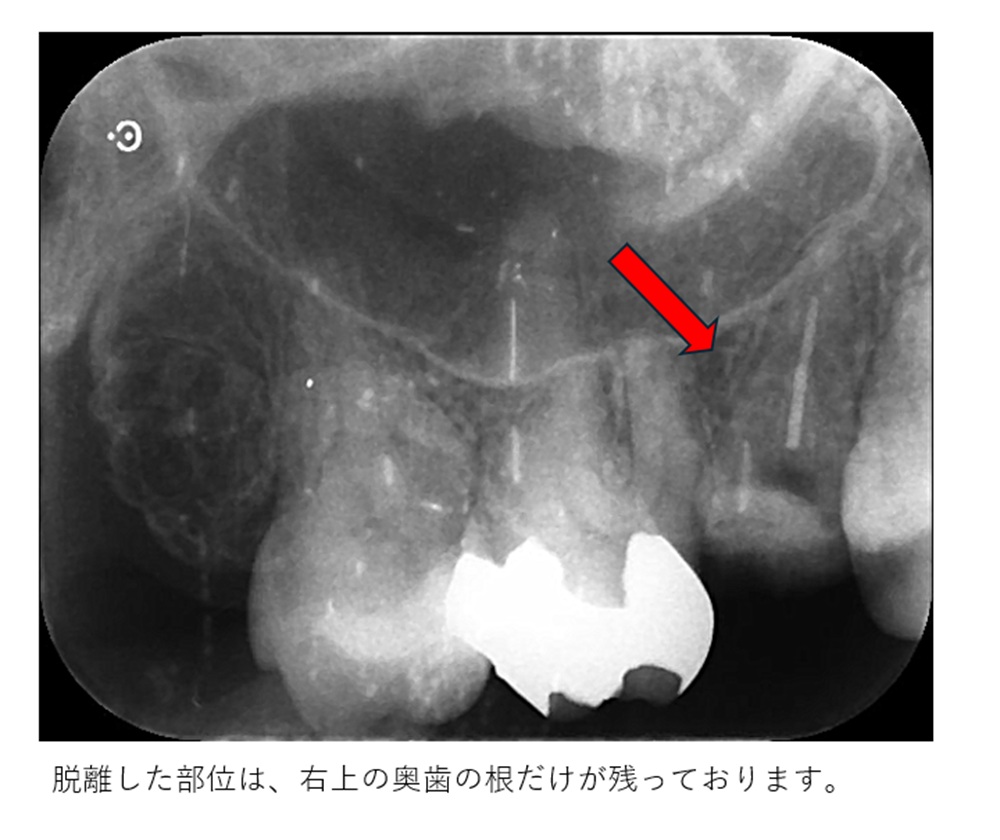

トラブル部位をレントゲンで診ると以下です。

通常は、保存できない状態です

歯槽骨より下に破折片の下縁があるためです。

レントゲン検査は、根の破折状態、根周囲の骨の状態や、破折した部位と歯槽骨の位置状態等を診ます。